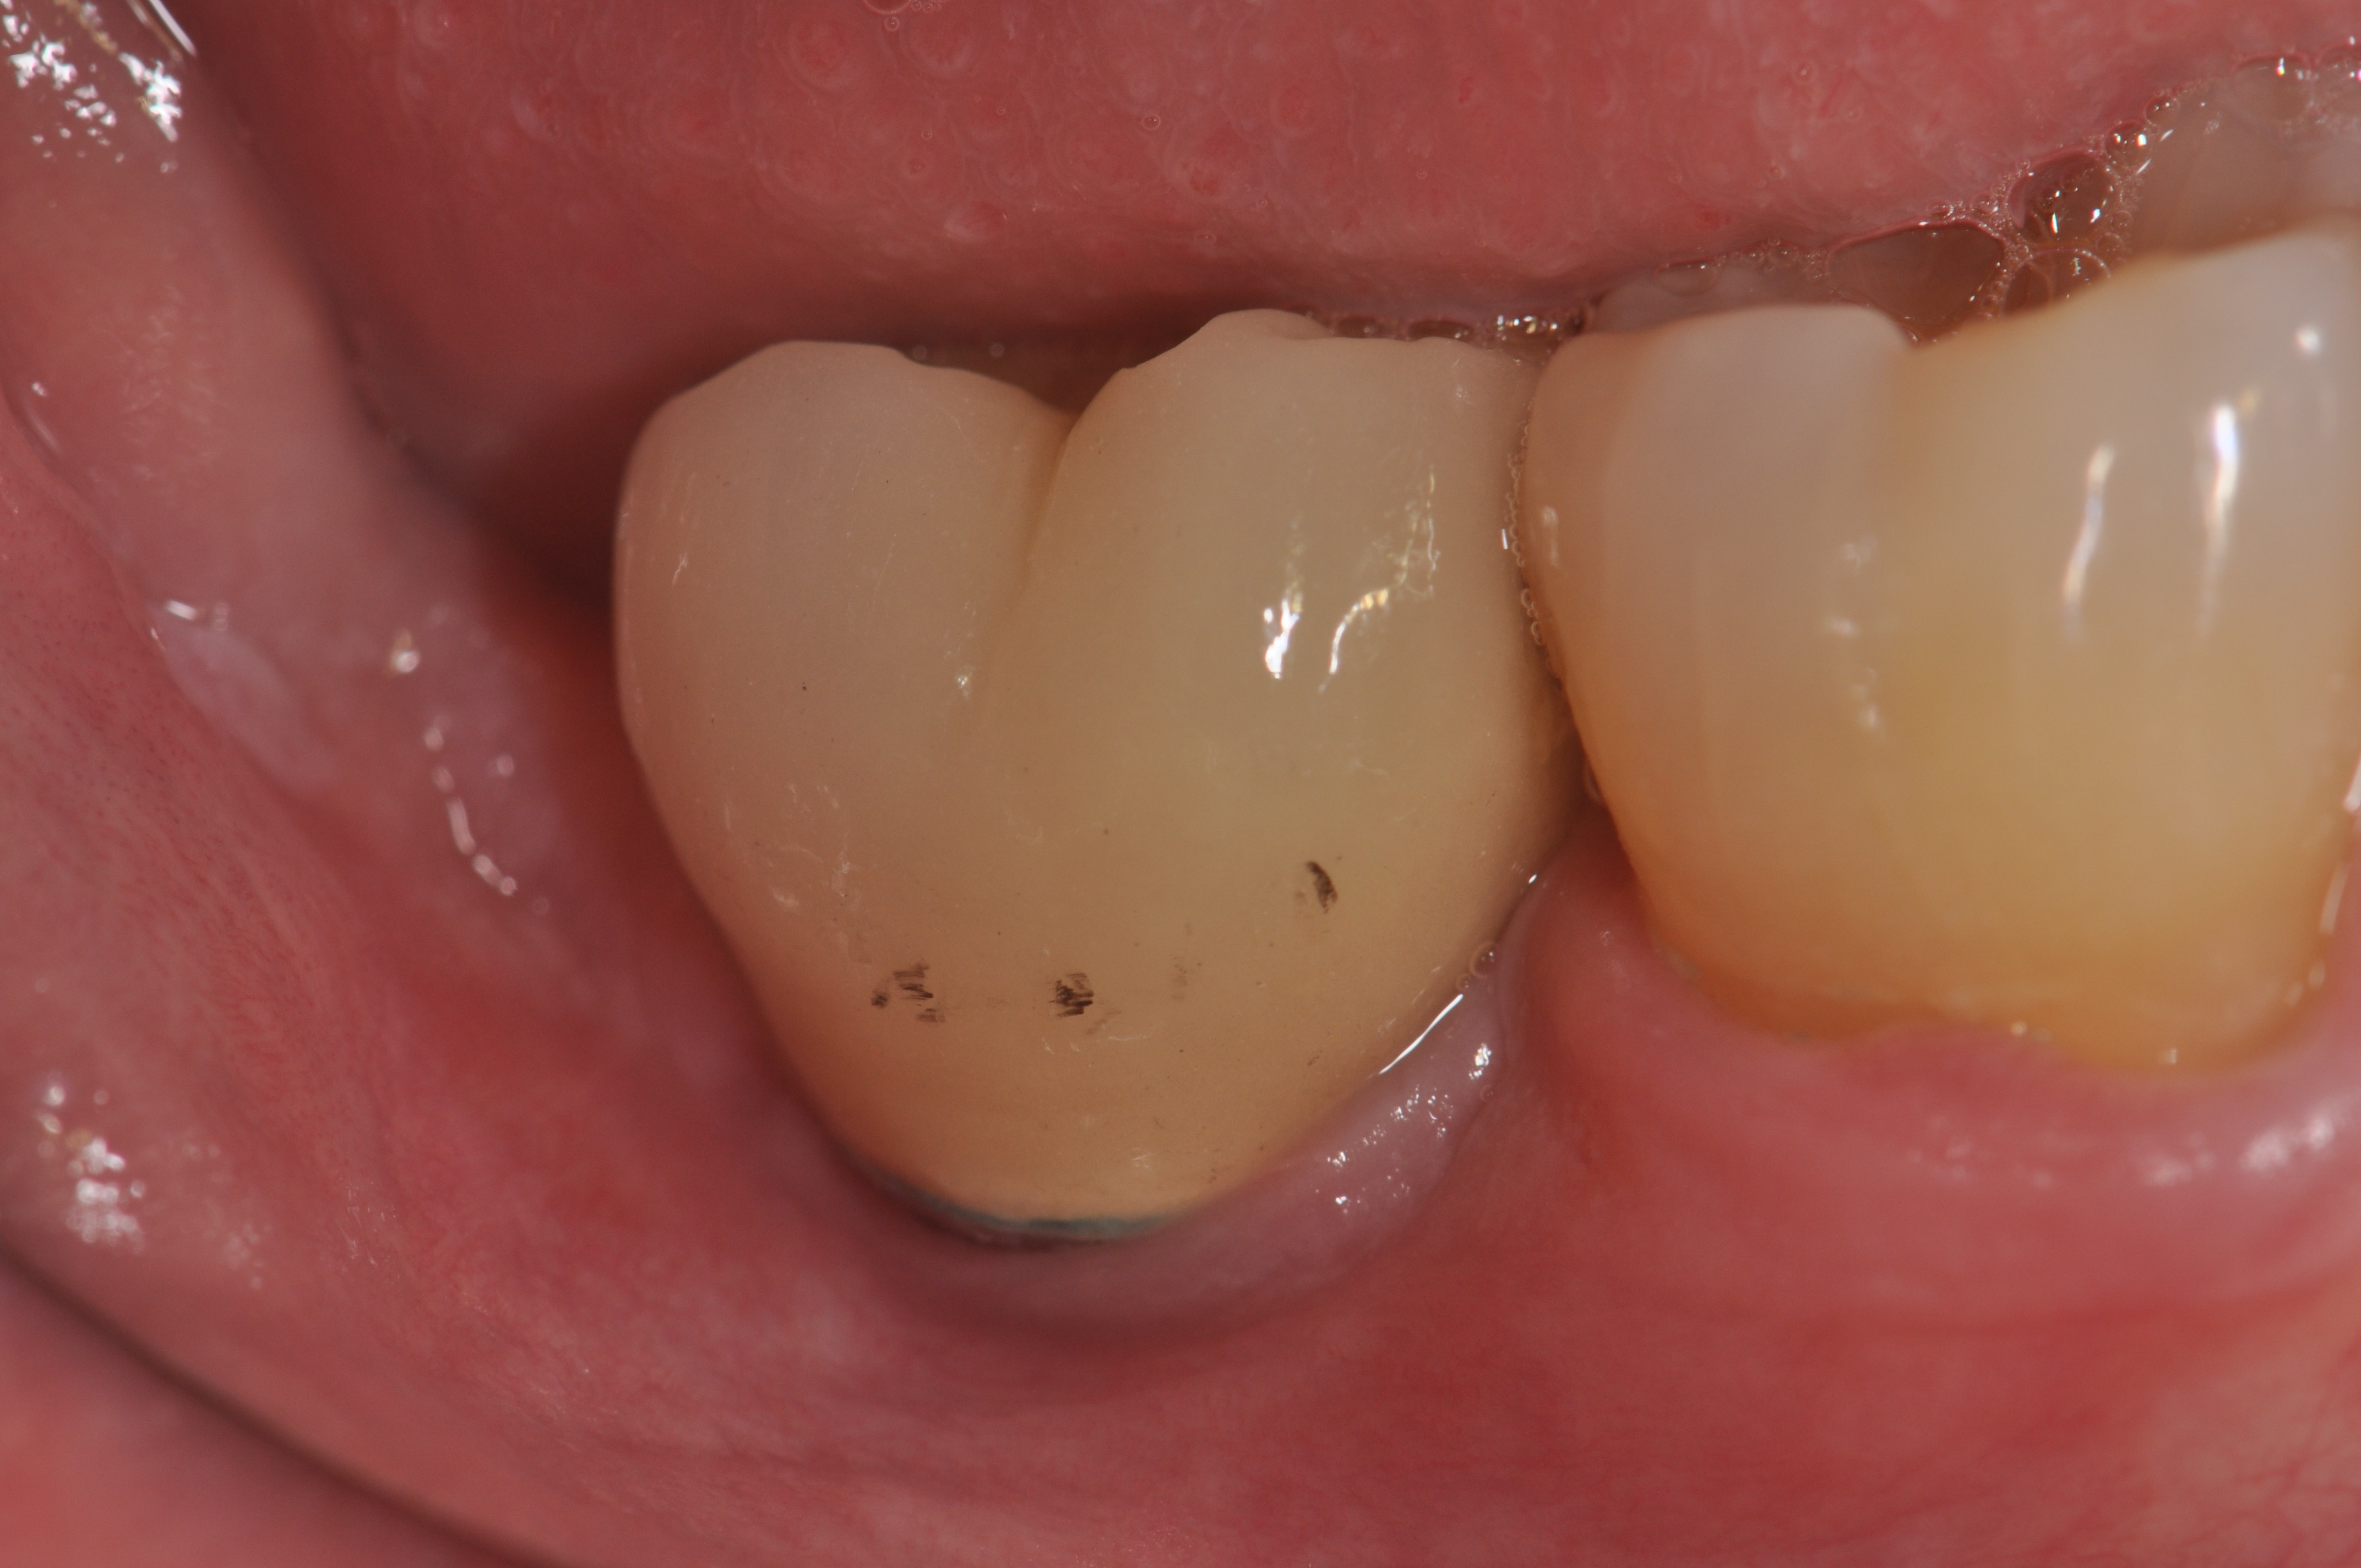

Pretreatment radiograph of a peri-implantitis

lesion on a 51-year-old male patient with a noncontributory medical history. The implant had been placed 3 years prior and presented with 8 mm pocketing with purulence.

Figure 1